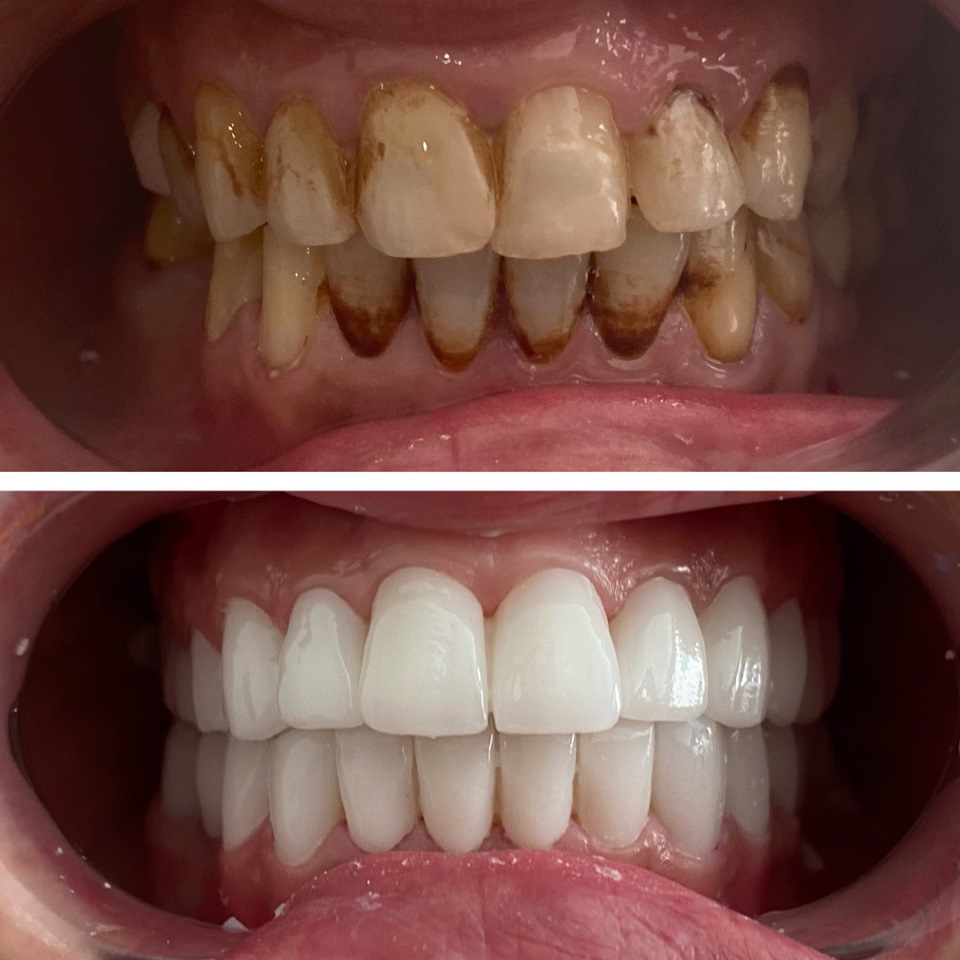

Smile Dental Clinic Turkey Gallery

Our Gallery and Happy Patients

Let’s make a change and put a perfect smile on your face with our dental clinic in Antalya/TURKEY.